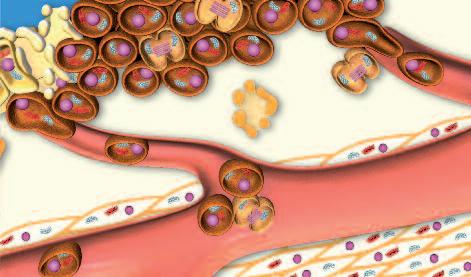

Normalmente, le cellule del nostro corpo sono inserite in una rete di collagene e di altre molecole del tessuto connettivo che le mantengono al loro posto. Affinché le cellule tumorali possano crescere, divenendo un tumore, e possano diffondersi in tutto il corpo, è necessario fendere questo isolamento del tessuto connettivo. A questo fine, ogni cellula del cancro produce ‘forbici biologiche’, ovvero degli enzimi proteolitici in grado di digerire il tessuto connettivo che circonda le cellule tumorali.

In caso di infezione polmonare, i globuli bianchi, che giungono con il flusso del sangue, attraversano la parete dei vasi sanguigni, piccoli capillari polmonari, per trasferirsi poi nel tessuto polmonare, con l'aiuto di enzimi che dissolvono il collagene. Per raggiungere il sito dell’infezione nei polmoni (ad esempio, batteri o virus), i globuli bianchi devono essere in grado di migrare attraverso il tessuto polmonare Per far ciò, utilizzano lo stesso meccanismo per sciogliere il collagene, allentando il denso tessuto connettivo circostante e spostandosi attraverso il tessuto in modo molto simile descritto nel paragrafo precedente, la produzione di collagenasi agisce come un machete usato per aprire un varco attraverso la giungla.

Al termine della gravidanza e in previsione dell'allattamento per il neonato, il segnale ormonale ordina alle cellule del seno di 'avviare' la produzione di enzimi che digeriscono il collagene. Proprio come una ‘squadra di demolizione’ nella vita reale, il loro compito è quello di abbattere l'architettura esistente nel tessuto mammario al fine di consentire la costruzione del tessuto del ‘seno idoneo all’allattamento'. Nella pagina accanto è possibile osservare al microscopio i profondi cambiamenti morfologici (strutturali) che il tessuto mammaria subisce passando dalla fase normale alla fase di allattamento.

Le collagenasi, gli enzimi che digeriscono il collagene, sono prodotte da tutte le forme di cancro, indipendentemente dalla loro origine. L’illustrazione delle pagine a fianco mostra un esempio di questo processo: lo sviluppo del cancro al fegato.

Il meccanismo di dissoluzione del collagene svolge un ruolo importante quando le cellule tumorali migrano per formare tumori secondari in altri organi o parti del corpo. Questo tumore secondario è detto metastasi. L'illustrazione nella pagina a fianco mostra il processo di un tumore al fegato che genera metastasi ai polmoni.

Ogni tumore è circondato da una rete di piccoli vasi sanguigni (i capillari). Con l‘aiuto di enzimi che dissolvono il collagene, cellule tumorali individuali possono ‘forare’ il muro di questi capillari ed entrare nel flusso sanguigno Una volta all'interno del vaso sanguigno, le cellule tumorali vengono trasportate dal flusso di sangue, proprio come i globuli rossi o bianchi, e raggiungono altri organi.